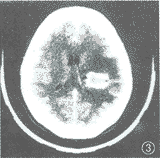

3、影像學檢查 B型超聲檢查對肝棘球蚴病的診斷具有重要價值可見到邊界明確的液性暗區,棋類可見到散在的光點或小光圈;對腎氣球油餅的診斷也有重要價值。CT掃描對肝棘球蚴病及腦、腎棘球蚴病的診斷也十分重要。此外腹部X線索平片上囊壁的圓形鈣化陰影及骨X線片上囊性陰影對診斷也很有重要意義。

診斷 對於來自流行區而肝臟、肺、腎或腦部發現有占位性病變者,應首先疑及本病而作進一步檢查。肝B超與CT掃描發現囊腫,有助於診斷。如肺棘球蚴病破入支氣管,患者咯出粉皮樣物質,顯微鏡下查到粉皮樣狀物,頭節或小鉤可確定診斷。 肝棘球蚴病應與非寄生蟲性肝囊腫相鑑別,腎棘球蚴病需與腎囊腫相鑑別。腦棘球蚴病需與腦囊尾蚴病、腦轉移瘤相鑑別。